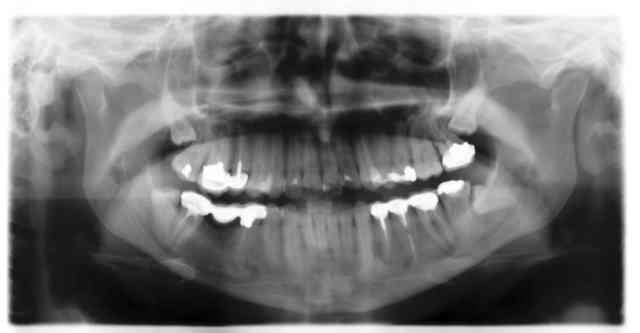

sans commentaire ...

de très belles dévitalisations remboursées au tarif de convention français ,j'espère !!!!!!!!!!!! Ça vaut pas plus.

Mouais, enfin j'ai vu passer des OPT bien plus scandaleuses "Made in France" également...

Ce que je veux dire, c'est qu'il n'est pas nécessaire de partir si loin pour voir ce genre de pano. C'est tout .Vos "analyses politiques" me paraissent hasardeuses.

J'ai déjà vu bien bien pire... Endo aussi naze mais avec des couronnes bien pire que ça dessus...

Et pourtant made in France.

il suffit de regarder la radio de Ceramik dans son post intitulé "alors, hop?" pour voir que des endos pourries il y en a partout! et pourtant, les incisives inférieures sont plus faciles a traiter que les molaires.

+1, des cas merdique, il y a en partout.

Des cas merdiques y'en a partout...mais dans certains endroits plus qu'ailleurs....